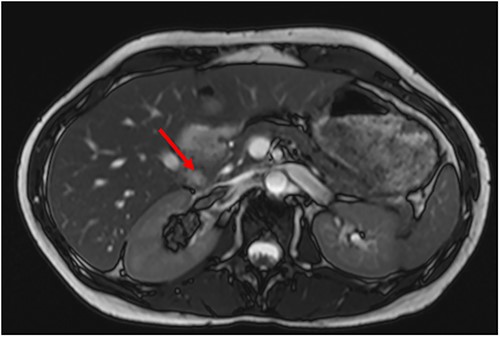

A 34-year-old female presented with acute onset left-sided chest pain and was found to have an occlusive PE in the left lower lobe. She was initiated on a heparin infusion. Imaging partially revealed a mixed-density lesion in the right kidney, which was further evaluated with a dedicated computed tomography (CT) scan and magnetic resonance imaging (MRI). This demonstrated concern for an AML involving the upper pole of the right kidney, with extension of tumor thrombus into the right renal vein and IVC (Figs 1 and 2). At this point, surgical oncology and cardiothoracic surgery (CTS) were involved to discuss resection. An echocardiogram confirmed that the tumor thrombus did not extend into the cavoatrial junction. MRI of the brain was ordered to rule out a rare presentation of tuberous sclerosis. Percutaneous renal biopsy demonstrated AML with epithelioid features. She was transitioned to therapeutic Lovenox and discharged with plans for surgical resection within the following week.

Preoperative MRI with tumor thrombus extension into right renal vein.